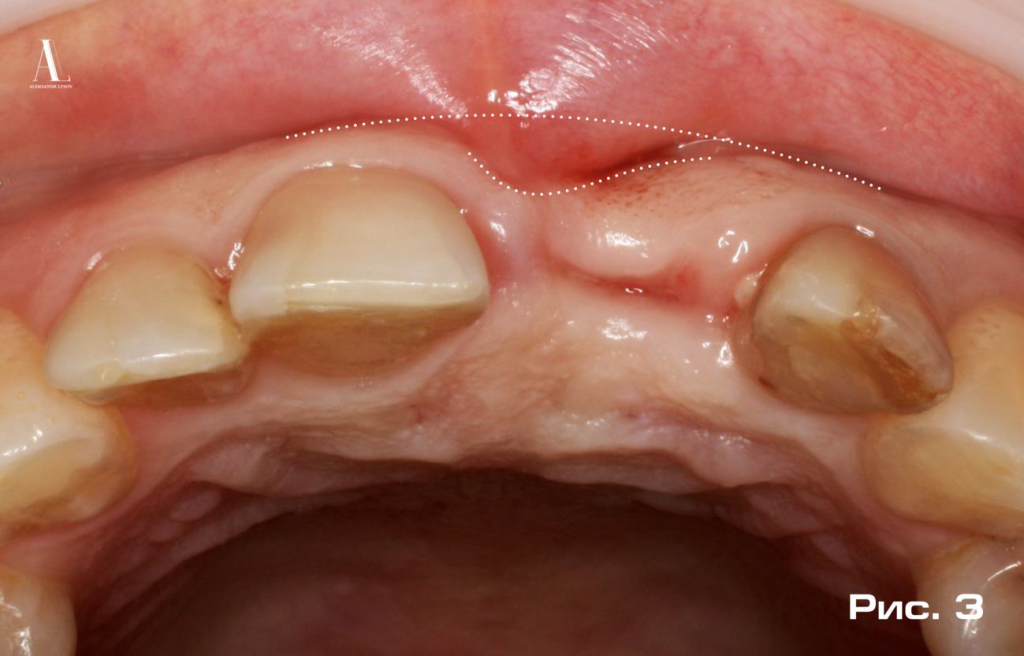

Отсутствие костной поддержки привело к образованию выраженного дефекта мягких тканей альвеолярного отростка (Рис. 3).